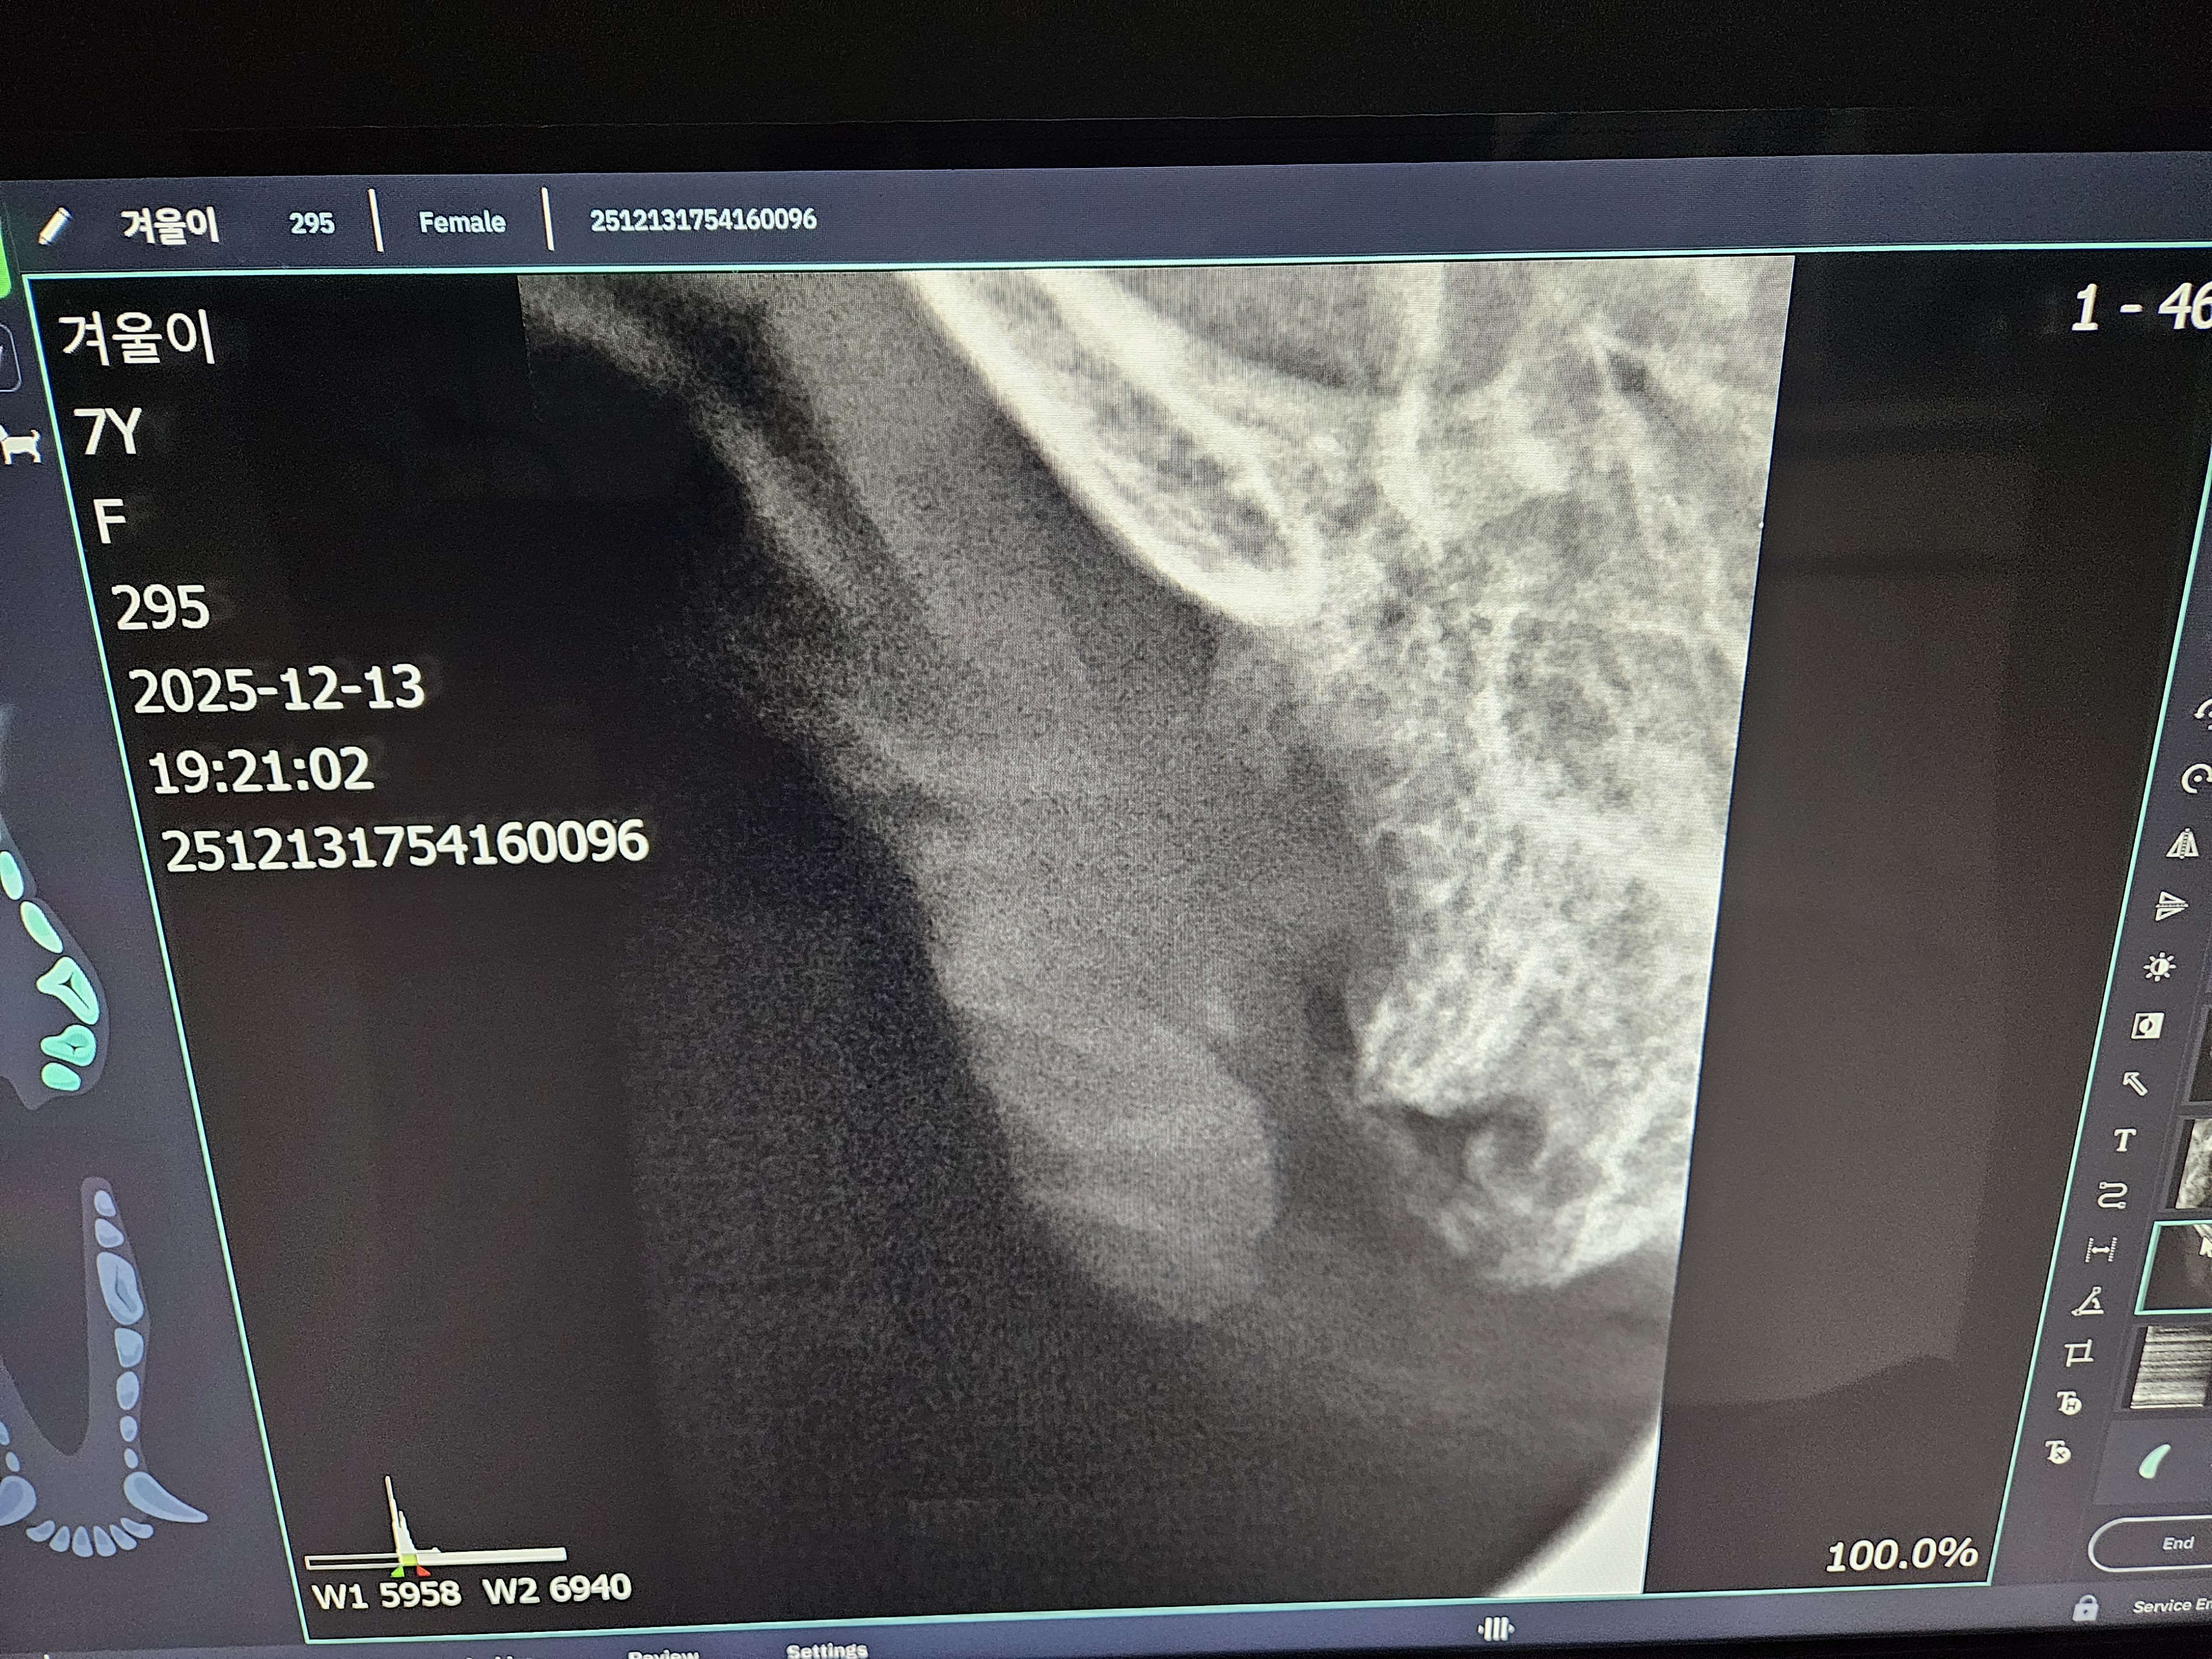

*치아 엑스레이 사진 입니다.

| 치료과정 | 겨울이 염증 수치가 엄청 높았습니다. 보통 정상 수치가 5까지인데 109정도로 엄청 높게 나왔다고 합니다. 염증 수치 같은 경우는 단점이 어떤 부위에 문제가 있는지를 나타내는 수치는 아님. 그런데 겨울이는 구강 안쪽이 엄청 빨개졌었음. 그래서 구내염에 의한 급성염증 수치라고 생각하면 되고, 마취 전에 한 검사는 간수치랑 신장 수치를 체크해주셨는데 콩팥이나 다른 부위는 기능이 정상이라고 하셨습니다. 겨울이 같은 경우는 밥을 잘 못먹었을 뿐이지 간수치나 신장 수치는 특이사항이 없다고 하셨습니다. 겨울이가 입원한 날 빈혈이 너무 심해가지고 수액을 맞았습니다. 그런데 적혈구 개체수도 부족해서 계속 수액을 맞을 수가 없었습니다. 혈액의 적혈구가 부족한혈액이 점점 많아지는 거예요. 항생제 수액으로 마무리 했다고 하셨고,급성 염증 수치는 시간이 지남에 따라서 무조건 좋아진다고 하셨는데, 약은 항생제와 염증 가라앉히는 소염제를 처방해준다고 하셨습니다. 치아 엑스레이 찍은 결과 치조골이라고 해서 이빨에 잡고 있는 뿌리가 어 다 녹아 있었고,그래서 이런 부분들이 이빨의 기능을 상실한 채로 그냥 이가욱씬욱씬한 상태로 있었을거고, 그래서 이빨을 뽑아야 하는 상태라고 하셨습니다. 송곳니는 부러져 있는 부위도 있어서 그런 이빨들은 뿌리 안남기고, 제거를 하셨다고 했습니다. 이빨 자체가 약한 상태이고 전체적으로 발치를 다 한 상태라고 하셨습니다. |